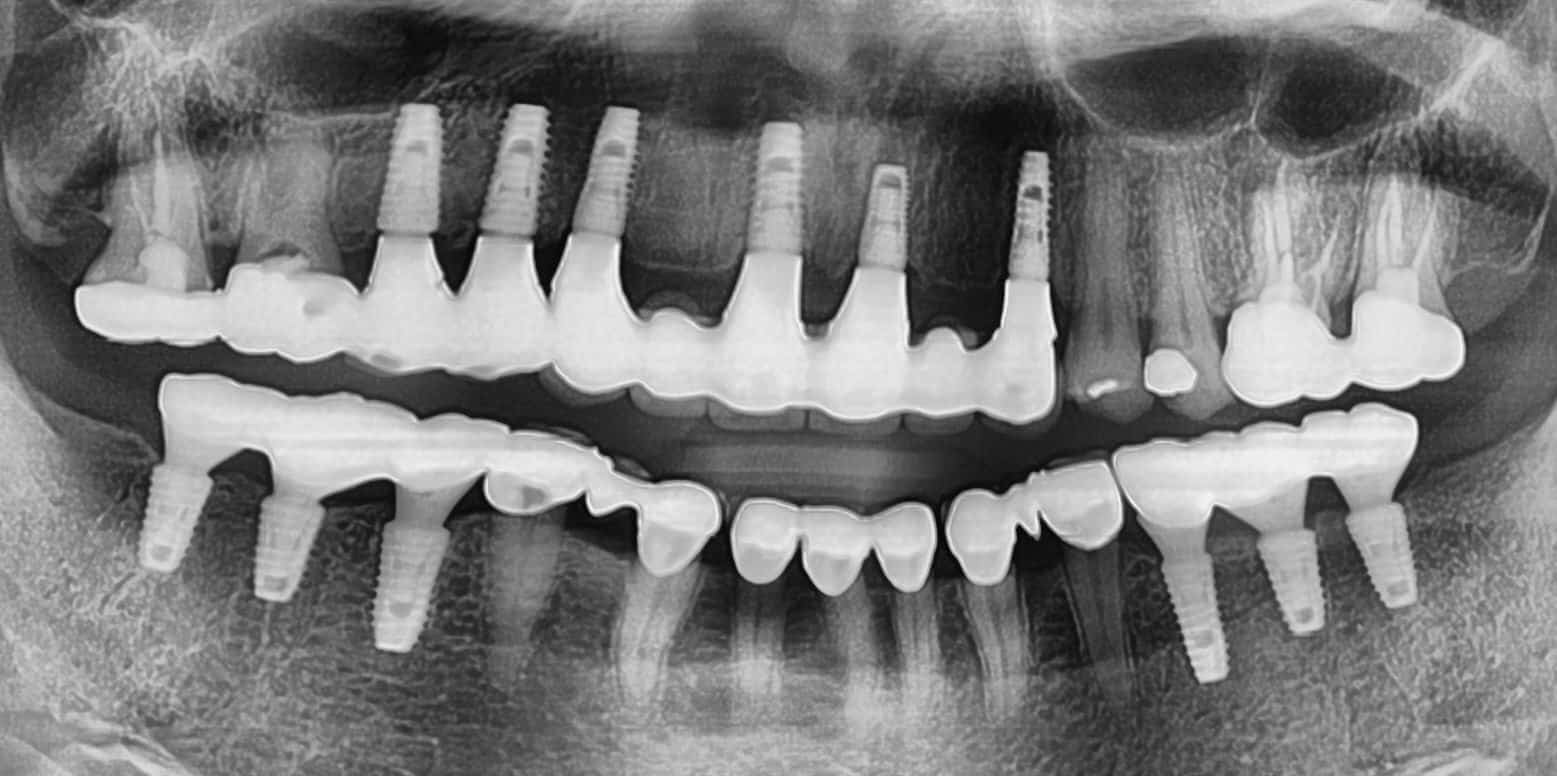

Dr. Lee is truly the best dentist I've ever seen. He placed my implant, and I couldn't be happier. His genuine care for my comfort and safety made all the difference. So glad I finally switched to this practice!